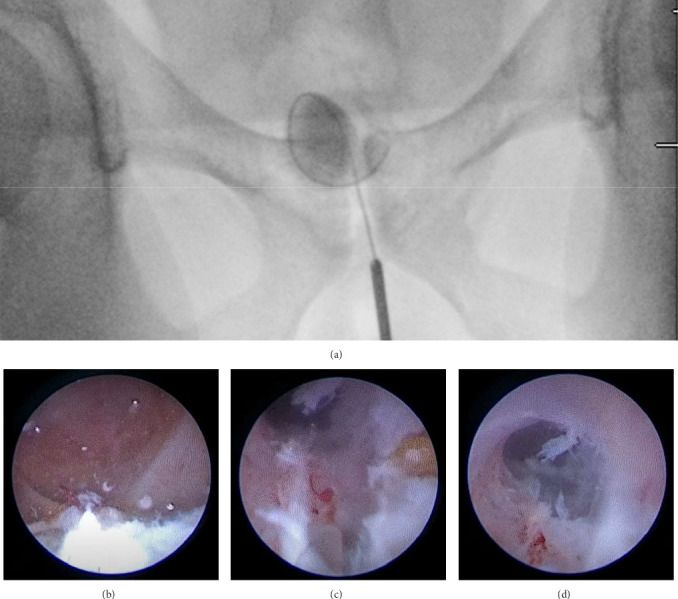

Seminal vesicle cyst (SVC) is a rare condition that can arise from congenital or acquired causes. In this report, we describe the case of a 33-year-old male who was incidentally discovered to have SVC and seminal vesicle stones following complaints of abdominal pain. He presented to the emergency department with these symptoms, which prompted further investigation and diagnosis. Computerized tomography (CT) scan revealed diverticulitis and a fluid attenuation lesion within the right aspect of the prostate gland. He was referred to urology, and further evaluation showed a right SVC of 1.8 × 1.5 × 1.5 cm on magnetic resonance imaging (MRI). The patient underwent endoscopic drainage of the SVC via transurethral seminal vesiculoscopy (TRU-SVS) and holmium laser incision. Three stones ranging from 2 to 4 mm were identified and removed with N-gage basket from the seminal vesicle resulting in successful removal of the stones and restoration of the ejaculatory duct's patency. Follow-up visits showed resolution of pain and an improvement in semen volume. This case report highlights the importance of considering SVC as a differential diagnosis in male patients presenting with such symptoms. TRU-SVS is a feasible and effective treatment option for SVC and associated seminal vesicle stones.